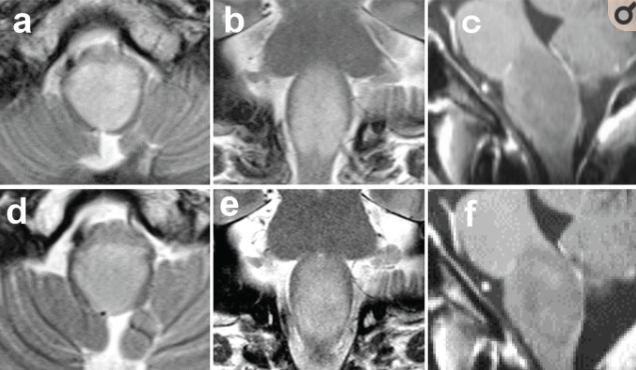

46岁男性,2个月头晕,随后出现头痛、麻痹、四肢感觉异常、发声困难和吞咽困难。一个月后,步态紊乱,食欲减退。磁共振成像(MRI)显示延髓T2-WI呈弥漫性高强度病变(图1a, b),病灶t1 -加权钆(Gd)未增强(图1c)。正电子发射断层扫描(PET)显示病变部位11c -蛋氨酸和18f -氟脱氧葡萄糖(FDG)呈负积累(数据未显示)。入院时,神经系统检查发现声音嘶哑、吞咽困难、咽反射丧失、声带麻痹、四肢麻痹和感觉异常。入院时Karnofsky表现状态(KPS)量表为40。为了进行病理诊断并确定治疗策略,患者进行了开放式活检。经枕下骨瓣切除术和C1椎板切除术,暴露延髓。延髓肿胀。在四脑室底正中沟处进行髓质切口,获得少量组织样本。术后CT 和t2加权MRI显示较小范围的颅骨切除术和活检。患者术后症状没有恶化。

图1磁共振成像(MRI)。a, b:初始t2加权MRI (T2-WI)示延髓弥漫性浸润性病变(a:轴位面,b:冠状面)。c:初始t1加权钆(Gd)增强MRI (T1-Gd)显示肿瘤几乎没有增强(c:矢状面)。d f: 6个月后,T2-WI未见改变(d轴面,e冠状面),T1-Gd病灶未见增强(f矢状面)。采用椭球形方法比较肿瘤体积。治疗前肿瘤体积与治疗6个月后无明显差异。

术后放射治疗(总计50 Gy/25天),同时替莫唑胺(TMZ)化疗75 mg/m2/天(140 mg/天),并联合皮质类固醇治疗。出院后到我院继续接受TMZ辅助化疗维持(一开始150mg /m2, 5天/28天,二次200mg /m2, 5天/28天)。在放化疗期间,患者进行了康复治疗。步态障碍和吞咽困难部分好转,KPS增加80。从较初的6个月治疗后随访MRI显示小的变化发现,稍微增强区域病变(图1 d-f)。而椭球形法比较肿瘤体积分析,治疗前肿瘤体积与治疗6个月后肿瘤体积无差异。